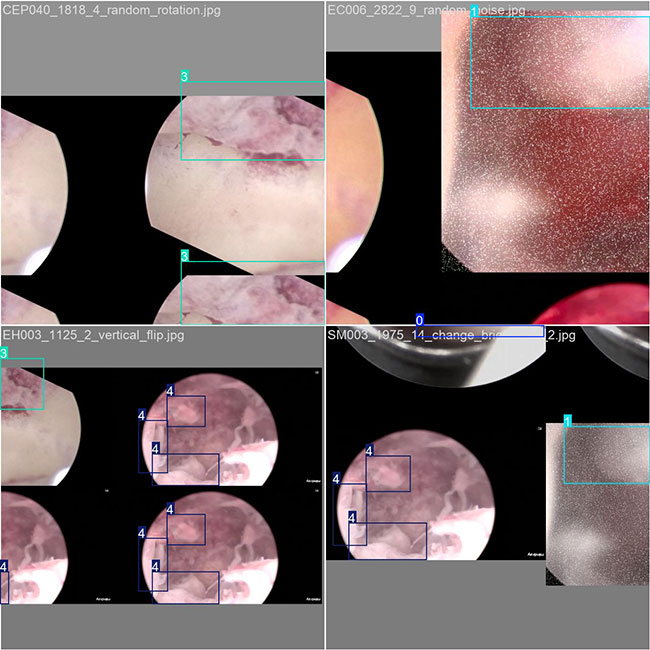

目标检测训练数据可视化

目标检测训练过程中,模型对数据的可视化结果,主要展示了多个类别目标的检测边框和类别标注情况。整体检测表现较好,但可以通过优化标注和模型训练进一步提升精度和鲁棒性。